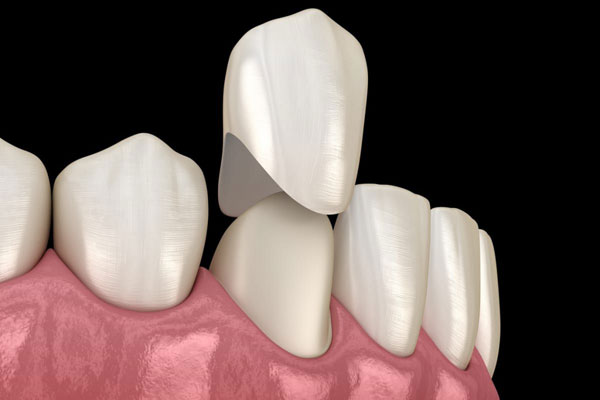

ЗУБНЫЕ ПРОТЕЗЫ, НЕ НАРУШАЮЩИЕ ДИКЦИЮ, ПОМОГАЮТ ПАЦИЕНТАМ ВЕРНУТЬСЯ К ПОЛНОЦЕННОЙ ЖИЗНИ

НАУЧНЫЕ ПОДХОДЫ В СТОМАТОЛОГИИ

Медики РязГМУ разработали челюстной протез нового поколения для реабилитации пациентов